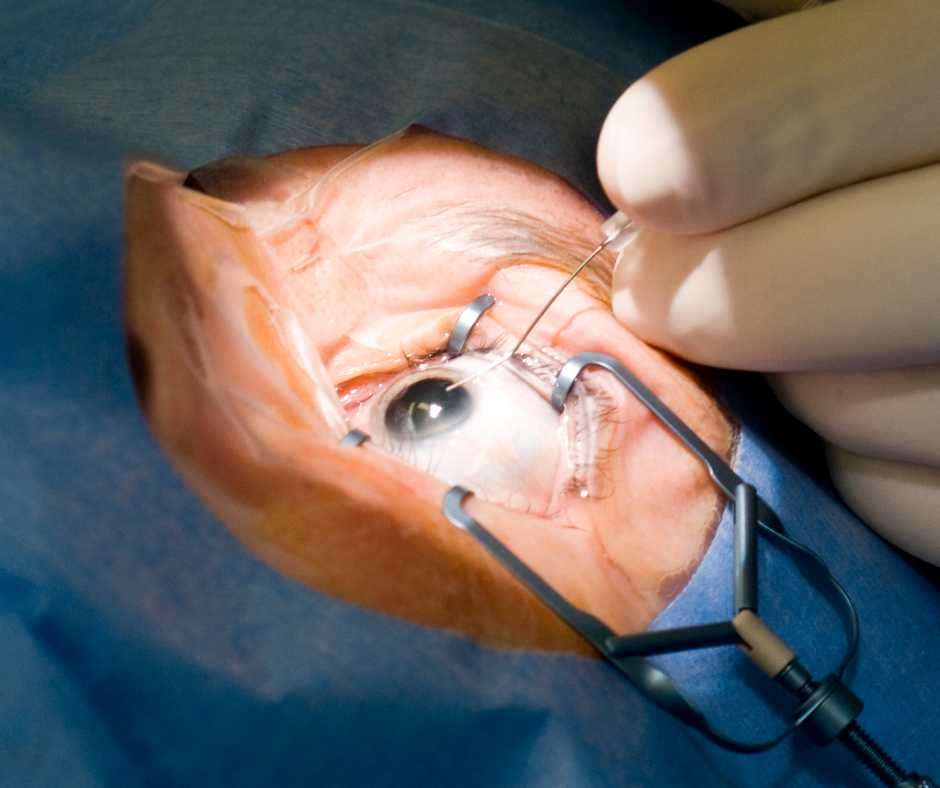

At Chugh Eye Surgery Centre, we specialize in advanced Vitreo Retinal Surgeries, including all types of vitrectomies and retinal detachment procedures. Our expert team uses cutting-edge technology to restore and preserve vision affected by complex retinal conditions.

Types of Surgeries We Perform

- Pars Plana Vitrectomy